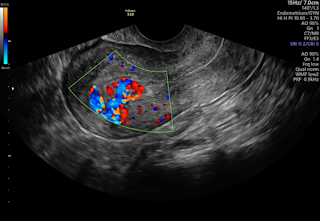

• Transvaginal Ultrasound

Transvaginal Ultrasound and it’s advantages

A transvaginal ultrasound is a medical imaging technique that uses sound waves to create images of the pelvic organs, including the uterus, ovaries, cervix, and...